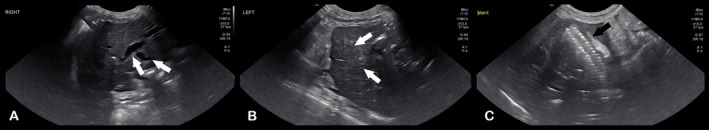

Post‐operative radiographs confirmed appropriate placement of the stent and the biliary drainage catheter (Figure 2). Abdominal ultrasonography showed asymmetric biliary tract decompression, with persistent right‐sided intrahepatic biliary tract dilatation (Figure 3A) and resolved left intrahepatic biliary tract dilatation (Figure 3B). The stent was visualized extending from the duodenal lumen through the CBD and into the left lateral liver lobe within the biliary tract (Figure 3C). A large volume of echogenic peritoneal effusion also was observed with hyperechoic mesenteric fat. Fluid analysis was consistent with mild mixed inflammation; no bacteria were seen; aerobic and anaerobic cultures were negative.

Improvement of hyperbilirubinemia and increased liver enzyme activities was noted post‐operatively (Table S1). Post‐operative radiographs showed an appropriately‐placed stent and biliary drainage tube (see Figure 5). A partial kink of the tubing was seen as it entered the body wall, but it was of no clinical consequence. Ultrasonography showed asymmetrical decompression of the intrahepatic biliary duct tracts, with ongoing right biliary obstruction and left‐sided decompression (Figure 6). Echogenic peritoneal effusion and hyperechogenicity of the cranial mesenteric fat also were noted.